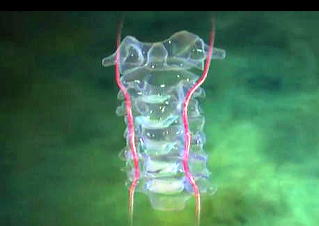

手術では、切開後、下の図にあるような第二頸椎を取り巻く筋肉や脊椎、末梢神経、動静脈などどへの損傷、影響を最低限に腰から採った骨を第一頸椎と第二頸椎の間に挟みつつ、4本のチタンスクリューと2本のチタンロッドで幹部を固定する。スクリューをうつ場所はドリルで穴を開けるという。 ◆手術の内容とInformed Consent 入院して一週間後、私は大手術を受けることになる。 手術の内容だが、折れて陥没した第二頸椎を自分の腰からとった骨を挟んで第一頸椎にチタン合金で構造化し固定化するもので、チタンのスクリューやロッドを6本使っている。まだ3次元画像はもらっていないが、後に術後のレントゲン写真を見せられた。これについても入手次第、掲載したい。 下は手術前夜に執刀医が私と妻との間で行われた Informed Choice and Consent時に示した手術の物理的な概念図である。構造設計図といってもよい。これは個室の前にあるカンファレンス室で執刀医、青山、妻の3人で1時間ほどかけ行われた。

そして翌日の11月19日午後から夜に及ぶ手術では、妻が個室(病室)に待機し、万一インフォームドコンセントの内容からはずれて麻酔、手術などをする場合、すぐに執刀医から妻に連絡が行くとされた。 手術では、当初通りに行われたこともあり、待機する妻への連絡は終了時までなかった。 ◆手術の具体的内容 C1が第一頸椎、C2が第二頸椎であり、上の図が側面図、下の図が組の後ろから見た側面図である。スクリュー4本、ロッド2本は素材がチタン合金であい、櫓を組んで第一、第二頸椎を腰から取った自分の骨を挟んで固定する。  主治医がInformed Consentで示した青山貞一手術の概念図(1) 慈恵医科大付属病院脳神経外科 2010.11.18 下は青山が上図を元にのちに作成したもの。ただし、下図は第二頸椎骨折、陥没後ではなく、健康な頸椎上にチタンのスクリューやロッドを書き加えている。さらに3次元で立体的に可視化しないとその構造は理解されにくい。  青山貞一による手術の概念図 下は使用するチタンスクリューのイメージである。   出典:http://www.sophiatech.co.jp/implans/screw_image/screw_image.html 手術ではたとえば以下のようにして使うことになる。ただし、以下はイメージ図。   それぞれの位置 背面図 出典:http://www.orihime.ne.jp/~one-/tekious.htm 手術の前々日、前日と2回に渡り麻酔専門医から何度も説明を受けた。麻酔の手順、心得などについても説明を受けた。 大手術は慈恵医科大学付属病院の脳神経外科、麻酔科などの専門医師5名による特別グループ構成で11月19日午後から夜にかけ行われた。 12時過ぎ、中央棟16階にある私の個室から看護師により車椅子で16階からエレベータを使って3階の手術に向かった。手術室到着後、麻酔専門医により点滴形式で全身麻酔が行われた。覚えているのはここまでである。 その後7-8時間はまったく記憶はなく夢も見ていない。 手術後すぐに、5階にある集中治療室(ICU)に移された。 ICUでは主動脈(Aライン)、静脈、末梢系はじめ各所に10本以上のチューブが体に差し込まれており、またオシッコなどの排出系もすべてチューブとなっていて身動きできなかった。入院後、一番きつかったのはこのときである。 慈恵医大病院中央棟のICUはかなりの数あり、手術を受ける患者には希望すると手術の前日までにICUを見学することができる。私は希望し前日にしっかり見学しICU側から説明も受けた。 肝腎な手術の内容は、上述のように落下転倒で折れ陥没した第二頸椎と第一頸椎の間に、腰から取った骨を挟み約2mm直径のチタン(金属)2本とそれにブリッジをかけるように固定することでした。チタンの棒は計4本使用している。 上記の手術内容についても、外来検査時から手術の前日まで、あらかじめ模型とグラフィックスをもとに主治医に何度も説明をしてもらった。 手術内容と方法には、当然のこととして代替案が多数ある。そのかかから医師と議論しながらひとつを選ぶことになった。代替案によりプラス、マイナス、リスク、費用が変わる。 また、もし手術で実際に首を開いたところ、第一案が難しい場合は第二案、第三案と次善の策についても優先順位を付けることになった。この説明と質疑にはかなりの時間が費やされた。この辺はInformed Consentの主要部分となる。 本来、第一頸椎と第二頸椎はそれぞれ独立して動くことで、人間は誰でも首が自由に回るのだが、第一と第二を固定化したので、手術によって直っても仰角、回転角ともに制限がある。リハビリなどにより健康な方の70%程度まで戻るかも知れないと言われた。 上述のように、私自身、3週間に及ぶ入院の中では、ICUから個室に移った20日が一番きつかった。翌日は一日安静にしていた。実のところ私が入院中に安静にしていたのは、この日(20日)くらいかも知れない。 19日夜から点滴が開始されていたが、20日の夕方から食事がだされた。食事と並行してブドウ糖などの点滴を行い栄養を体に送り込んだ。点滴にはブドウ糖とともに手術時の各種傷口に対応するための抗生剤が含まれる。 22日以降、手術に関連した痛みがかなり減ってきた。術後、一切の鎮痛剤を使っておらず看護師さんらはびっくりしている。痛みは人によって個人差があるようだ! ところで今回は、11日に東京都品川区にある旗の台脳神経外科に診察にでかけたときから、現在に至るまで徹底的にInformed choice and consentを心がけ、すべてに渡り主治医(脳神経外科執刀医、呼吸器主任、糖尿など生活習慣病関連の主任、麻酔主任)らからの説明を受け、その都度理解、認識した上で判断した。 たとえば呼吸機能を回復させようとすると血糖値やLDLが上昇するなど新たな問題が起こるが、それらを承知の上で何を優先するかが術前の大きなポイントとなる。これについても、私のここ数年の経験を伝えた。 医者側も驚いていたが、やはり患者や家族は医者任せ、看護師まかせではなく、主体性を持って対応することの大切さを実感している。 下は健康な人の第一頸椎(上)と第二頸椎(下)の側面図である。 第一頸椎 出典:http://video.about.com/backandneck/Cervical-Spine-Anatomy.htm 第二頸椎 出典:http://video.about.com/backandneck/Cervical-Spine-Anatomy.htm 下のレントゲン写真は術後に撮影したものである。 退院後初の検査時に主治医より提供を受けた。第一頸椎と第二頸椎の間に腰骨を挟み、チタン合金で第一頸椎(長いスクリュー)、第二頸椎(短いスクリュー)で固定している様子が3次元の立体図で良く分かる。  手術後の頸椎レントゲン写真(2010/12/13) 出典:東京慈恵会医科大学付属病院脳神経外科 以下は、CT及びMRIで見た手術個所の断層図である。退院時、希望していたCT及びMRI断層画像データをCD媒体で提供された。画像は専用ソフトだけでなくWindowsXP,7などのブラウザでも見れる。  出典:東京慈恵会医科大学付属病院脳神経外科 下はCT画像に見る第二頸椎に入れたチタンスクリュー(ネジ)。断層撮影なので部部しか見れない。  CT断層画像に見る青山貞一の手術後(2010年11月20日撮影)。 慈恵医大付属病院 下もCT画像に見る第二頸椎に入れたチタンスクリュー(ネジ)。断層撮影なので部部しか見れない。チタンスクリューは4本、チタンロッド(棒)は2本入れてある。  CT断層画像に見る青山貞一の手術後(2010年11月20日撮影)。 出典:慈恵医大付属病院脳神経外科  CT断層画像に見る青山貞一の手術後(2010年11月20日撮影)。 出典:慈恵医大付属病院脳神経外科  CT断層画像に見る青山貞一の手術後(2010年11月20日撮影)。 出典:慈恵医大付属病院脳神経外科  CT断層画像に見る青山貞一の手術後(2010年11月20日撮影)。 出典:慈恵医大付属病院脳神経外科  CT断層画像に見る青山貞一の手術後(2010年11月20日撮影)。 出典:慈恵医大付属病院脳神経外科 下は腰の骨の採取場所を示している。また手術時の切開位置を示している。首の裏を縦に12cmほど切開している。  主治医ががInformed Consentで示した青山貞一手術の概要図(2) 慈恵医科大付属病院脳神経外科 2010.11.18  頸椎を取り巻き上下に縦断する筋肉 出典:http://video.about.com/backandneck/Cervical-Spine-Anatomy.htm  頸椎と隣り合わせに上下に縦断する脊髄 出典:http://video.about.com/backandneck/Cervical-Spine-Anatomy.htm 万一動脈を切った場合は、すぐに輸血を開始するという。  頸椎と隣り合わせに上下に縦断する動脈 出典:http://video.about.com/backandneck/Cervical-Spine-Anatomy.htm 下は慈恵医大付属病院のCTで撮影した青山貞一の頸椎と隣り合わせに上下に縦断する動脈である。  CT断層画像に見る青山貞一の頸椎と隣り合わせに上下に縦断する動脈(撮影2010年11月17日)。 出典:慈恵医大付属病院脳神経外科 英国医学会で頸椎手術に関連し想定しているリスク(合併症を含む)を以下に示す。すなわち外科手術により物理的に幹部を固定化したとしても、将来、以下のようなリスクがないわけではないようだ。  出典:http://video.about.com/backandneck/Complications-of-Spinal-Surger.htm ◆全身麻酔による大手術 入院から一週間後の11月19日午後、全身麻酔後に大手術をすることになった。慈恵医科大学付属病院の中央棟3階にある手術室で手術を受ける。 手術の数日前から麻酔の専門医2名から説明を受ける。また看護師から手術当日の実務手順について資料をもとに説明を受ける。 お昼に病室がある16階から専用エレベータで手術室がある3階に直行し、その後、麻酔との対話の中で点滴により全身麻酔がおこなわれ、5名のチームによる手術が開始された。 慈恵医大脳神経外科の手術では全国でここだけ、手術中にCT断層撮影が可能とのことである。 午後8時過ぎ手術は終了し、5階の集中治療室(ICU)に移された。麻酔が切れた後、妻や池田さんと会話を交わした。大手術は大成功であった! 現在の麻酔技術の進歩はすさまじく、5分単位で全身麻酔をオンオフできるという。医師は麻酔技術は日進月歩で進歩しており、すばらしく切れがよいと言っていた。  慈恵医大病院中央棟3階にある手術室のイメージ 3階、4階が手術室。5階が集中治療室(ICU)、6階より上が病棟 出典:慈恵医大病院公式Web  集中治療室(ICU)の一部(イメージ) 出典:慈恵医大病院公式Web このように11月19日午後から夜に行われた手術では、当初予定の内容を関連する神経系、動脈系などに損傷を与えることなく実施できた。 ★手術成功のお知らせ(池田こみち) 術後の痛みだが、鎮痛剤を注射してもらうほどの耐えられない痛みは退院までなく、当初からあった後頭(こうとう)神経痛も次第に弱くなってきた。それ以外の痛みとしては、寝る角度により腰から骨を採った場所がちくりと痛むことがル程度である。 以下は青山貞一の手術を担当してくれた大橋医師のプロフィールです。